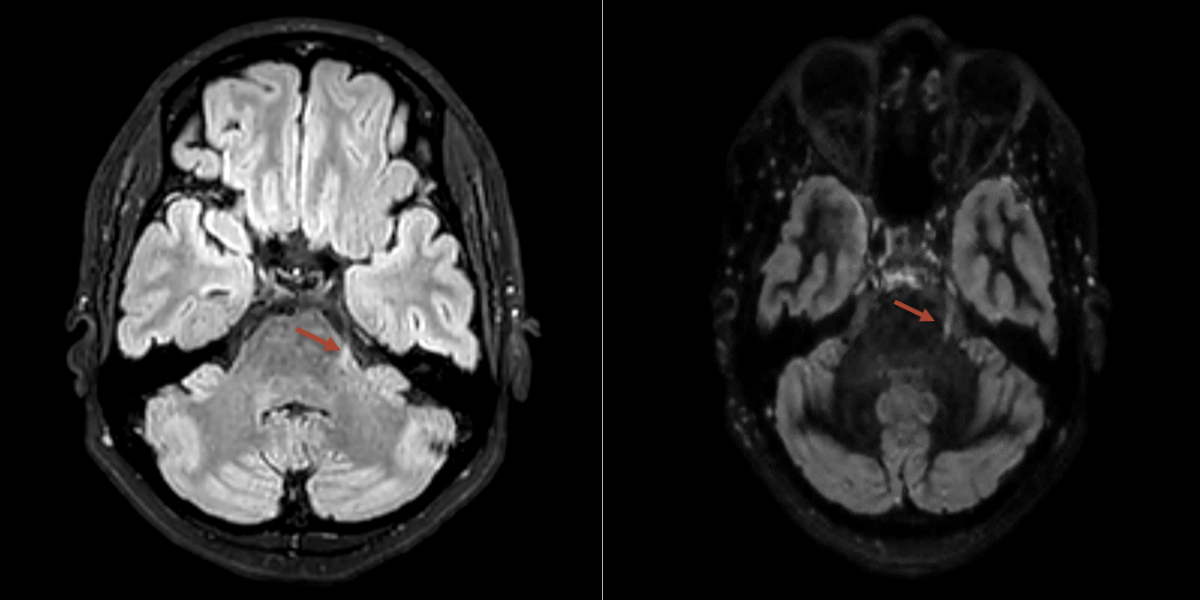

Every patient with suspected trigeminal neuralgia requires imaging to distinguish between classic trigeminal neuralgia and secondary causes. The current gold standard is magnetic resonance imaging (MRI), including high-resolution constructive interference in steady-state (CISS) sequences to exclude neurovascular compression, T2 sequences to detect possible inflammatory processes and angiography [9, 10] (figures 2, 3, 4). When assessing a possible pathological neurovascular contact, it is important (for planning potential surgical procedures) to distinguish between nerve displacement and atrophy [12].

Figure 2MRI showing an multiple sclerosis lesion at the exit of the left trigeminal nerve in the area of the lateral pons (red arrow).

Figure 3MRI showing pathological neurovascular contact between the right superior cerebellar artery (red arrow) and the trigeminal nerve (yellow arrow).